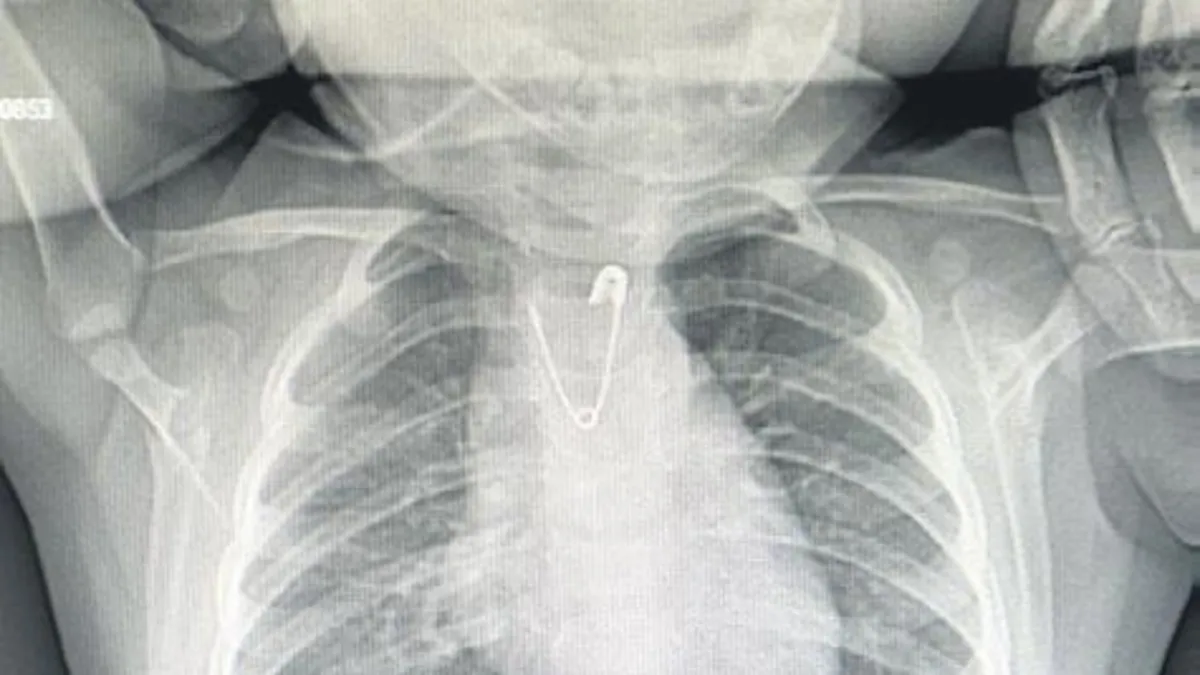

Bebeğin akciğer grafisi çekilerek, çengelli iğnenin yemek borusuna kaçtığı görüldü.

Ankara Kahramankazan'da 10 aylık kız bebeğine annesi nazardan korunması için yakasına çengelli iğne ile nazar boncuğu taktı. Küçük kız, ucu açık bir şekilde bırakılan çengelli iğneyi ağzına attı.

Daha sonra iğneyi yutunca kusmaya başladı. Anne, küçük kızını hemen hastaneye kaldırdı. Çekilen röntgen filminde iğnenin çocuğun boğazına takıldığı saptandı. Ameliyatı yapan Çocuk Cerrahisi Uzmanı Doç. Dr. Doğuş Çalışkan, "İğnenin ucunun açık olması, çıkarılması için zorluk teşkil etti. Bu işlem yapılırken yemek borusunda yırtık, kanama ve ciddi hayati tehlike yaratan durumlar söz konusuydu. Ama işlemi başarıyla gerçekleştirdik" ifadesini kullandı.